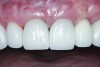

The master cast and abutment were returned to the laboratory for fabrication of the restoration (Figure 15). An all-ceramic crown (e.max®, Ivoclar Vivadent) was fabricated on the custom abutment; it matched the contours of the adjacent central incisor. After completion of custom shading, the definitive abutment and crown were returned to the restorative dentist. The abutment was tried in (Figure 16), and a radiograph was taken to confirm complete seating between the abutment/implant and the crown/abutment. The definitive abutment screw was torqued to 20 Ncm, and the screw-access opening was blocked out with Teflon tape.

The crown was inserted and secured with a luting composite (Multilink® Automix, Ivoclar Vivadent) (Figure 17); a radiograph confirmed complete removal of excess cement (Figure 18). At the 4-month follow-up appointment, the soft tissues were healed within normal limits, and the patient was pleased with the esthetic outcome of the definitive restoration (Figure 19 and Figure 20).

Fig 16. Try-in of the definitive titanium-nitride–coated abutment.

Figure 16

Fig 19 and Fig 20. Four-month follow-up appointment. The soft tissues had healed within normal limits (Fig 19), and the patient was pleased with the esthetic outcome of the definitive restoration (Fig 20).